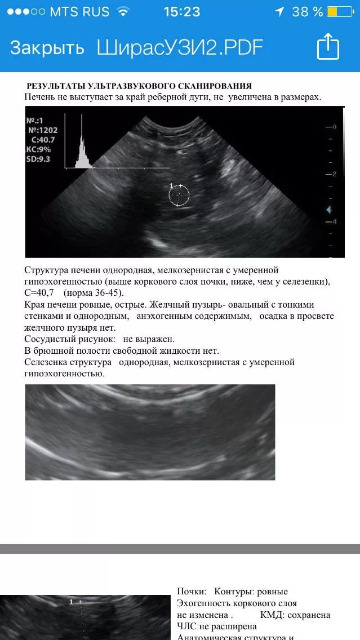

Я так понимаю, судя про образцу заключения, вы проводите ультразвуковую денситометрию печени и селезенки на обычном УЗ-сканере?

И еще у меня второй вопрос по тому же образцу заключения - что изображено на втором снимке?